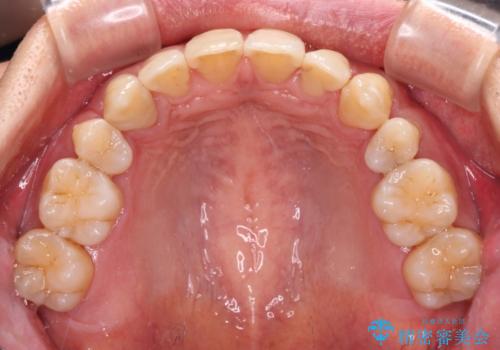

叢生が強い場合、抜歯スペースが叢生を解消するために消費されるため、口元の突出感があまり改善されないことがあります。

今回の治療では、奥歯が前方に傾斜した歯並びだったため、奥に起き上がることで歯列が後方に移動し、横側からも口元が引っ込んだ感じが分かるほど改善されました。